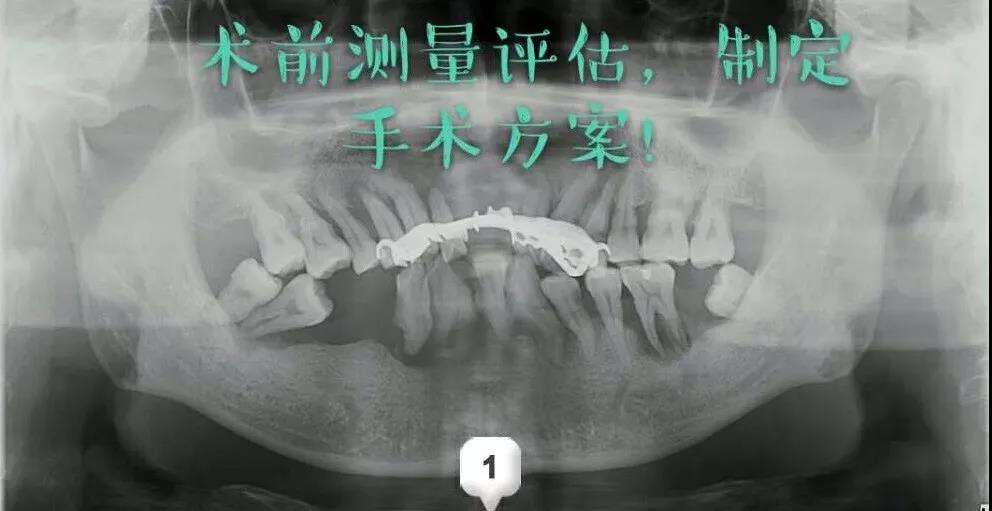

第一次耗时两个多小时:先进行了术前的测量评估,指定手术方案;术中采用数字化种牙导板,精准定位;逐级备洞,植入植体,扭力复合完成植入上半口。